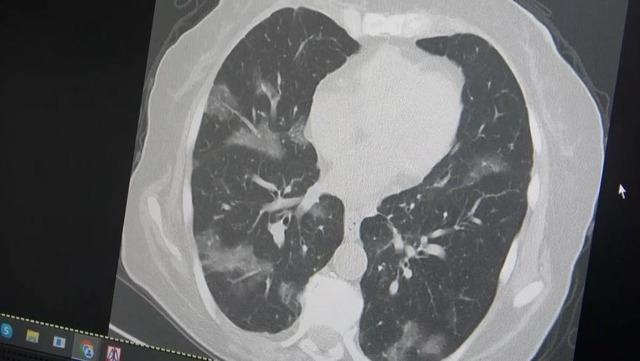

Bir kanser hastasının akciğerlerinden örnek veren Özkaya, şöyle konuştu: “60 yaş üstü olması ve kemoterapi görmesi nedeniyle virüsün akciğerlere rahatlıkla indiğini görüyoruz. Bu yaza damgasını vuracak yeni virüsün bu olduğunu düşünüyoruz” dedi.